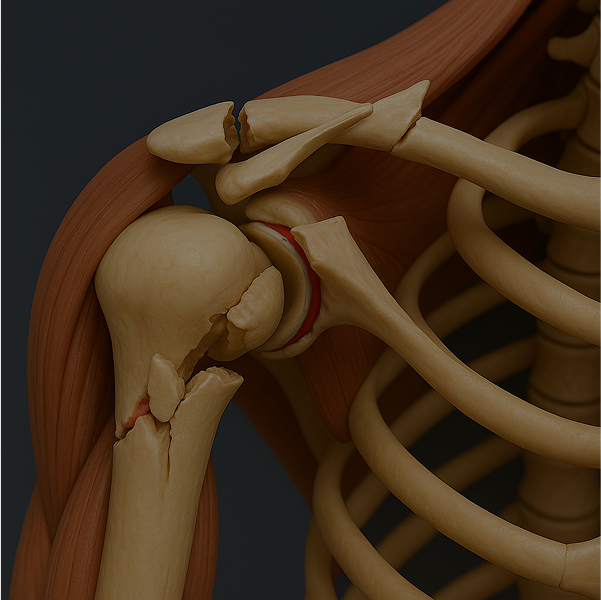

The shoulder is a complex joint made up of various structures that can become injured or inflamed.

Common causes of shoulder pain include

or tears

or adhesive capsulitis

Identifying the root cause of your shoulder pain is essential.